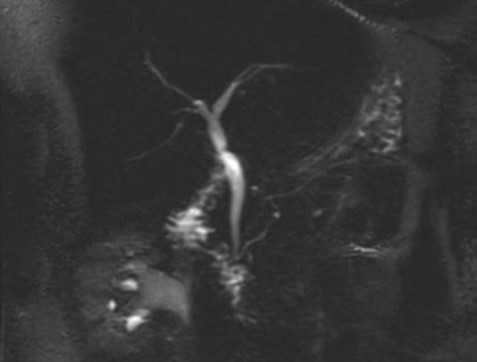

МРТ брюшной полости в корональной плоскости. Очаговые кистозные образования печени паразитарной природы, округлой формы, с четкими и неровными контурами.